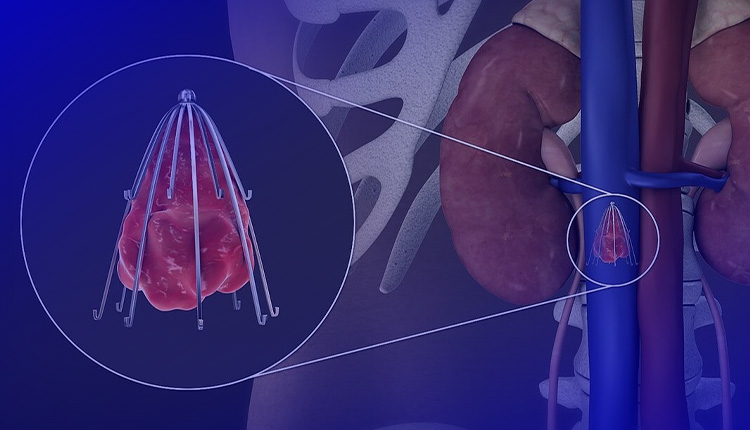

فیلتر ivc قلبی یا فیلتر ورید اجوف تحتانی (Inferior Vena Cava Filter یا IVC Filter) یک دستگاه پزشکی کوچک است که در ورید اجوف تحتانی (IVC) قرار میگیرد تا لختههای خون را قبل از رسیدن به ریهها گیر بیندازد و از آمبولی ریوی (PE) جلوگیری کند. این فیلترها عمدتاً برای بیمارانی استفاده میشوند که VTE (ترومبوآمبولی وریدی) دارند اما نمیتوانند از ضد انعقادها استفاده کنند، مانند موارد خونریزی فعال یا جراحیهای پرخطر.

فیلتر ivc قلبی به دستههای دائمی، قابل بازیابی (retrievable)، convertible و bioconvertible تقسیم میشوند. اکثر مدلها از مواد مانند Nitinol یا stainless steel ساخته شدهاند و شکل مخروطی یا cage-like دارند.

روش قرارگیری فیلتر ivc قلبی (IVC Filter)

قرارگیری فیلتر ivc قلبییک روش کمتهاجمی (minimally invasive) است که معمولاً توسط رادیولوژیستهای مداخلهای (interventional radiologists) در اتاق آنژیوگرافی انجام میشود. این روش حدود ۳۰ تا ۶۰ دقیقه طول میکشد و اغلب سرپایی است (بیمار همان روز مرخص میشود). بیمار بیدار است اما با داروهای آرامبخش (conscious sedation) و بیحسی موضعی، درد احساس نمیکند.

راهنمایی اصلی با فلوروسکوپی (تصویربرداری زنده با اشعه ایکس) و تزریق ماده حاجب (contrast dye) برای دیدن وریدها انجام میشود. گاهی از اولتراسوند برای دسترسی اولیه استفاده میشود.

• موقعیت ایدهآل فیلتر: درست زیر وریدهای کلیوی (infrarenal) برای جلوگیری از انسداد

• sheath (لوله بزرگتر) روی وایر پیشرفته میشود تا به موقعیت مورد نظر برسد. - باز کردن (Deployment) فیلتر ivc قلبی:

• sheath عقب کشیده میشود تا فیلتر باز شود و با قلابها یا پاها به دیواره IVC بچسبد.